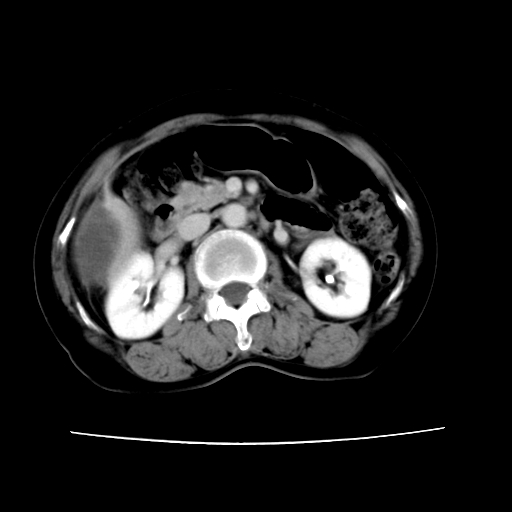

2008-11-10ct平扫(其间去中山医院诊治未行特殊治疗)

2008-11-10ct平扫见并肝内、血膜下血肿基本吸收,肝内低密度灶缩小。此时再做增强ct应有显着意义。对患者/医者都好!

从平扫+增强及治疗后复查片,病变明显缩小,不考虑肝癌出血可能,还是考虑为良性病变可能性大;单纯血肿并包膜下积液吧,病变强化没法解释,肝血管破裂出血吧,增强不符合典型血管瘤的表现,良性肿瘤破裂出血吧,复查片看来好像也不太支持(没做强化也不太好说)。本人还是考虑单纯肝内血肿并包膜下积液,强化是不是血管有外渗。

患者自6月至11月,如果是肝癌,没有经过特殊治疗,想必应该会有所进展吧,而不是ct所见,反而似有病灶减小的趋势。建议增强。